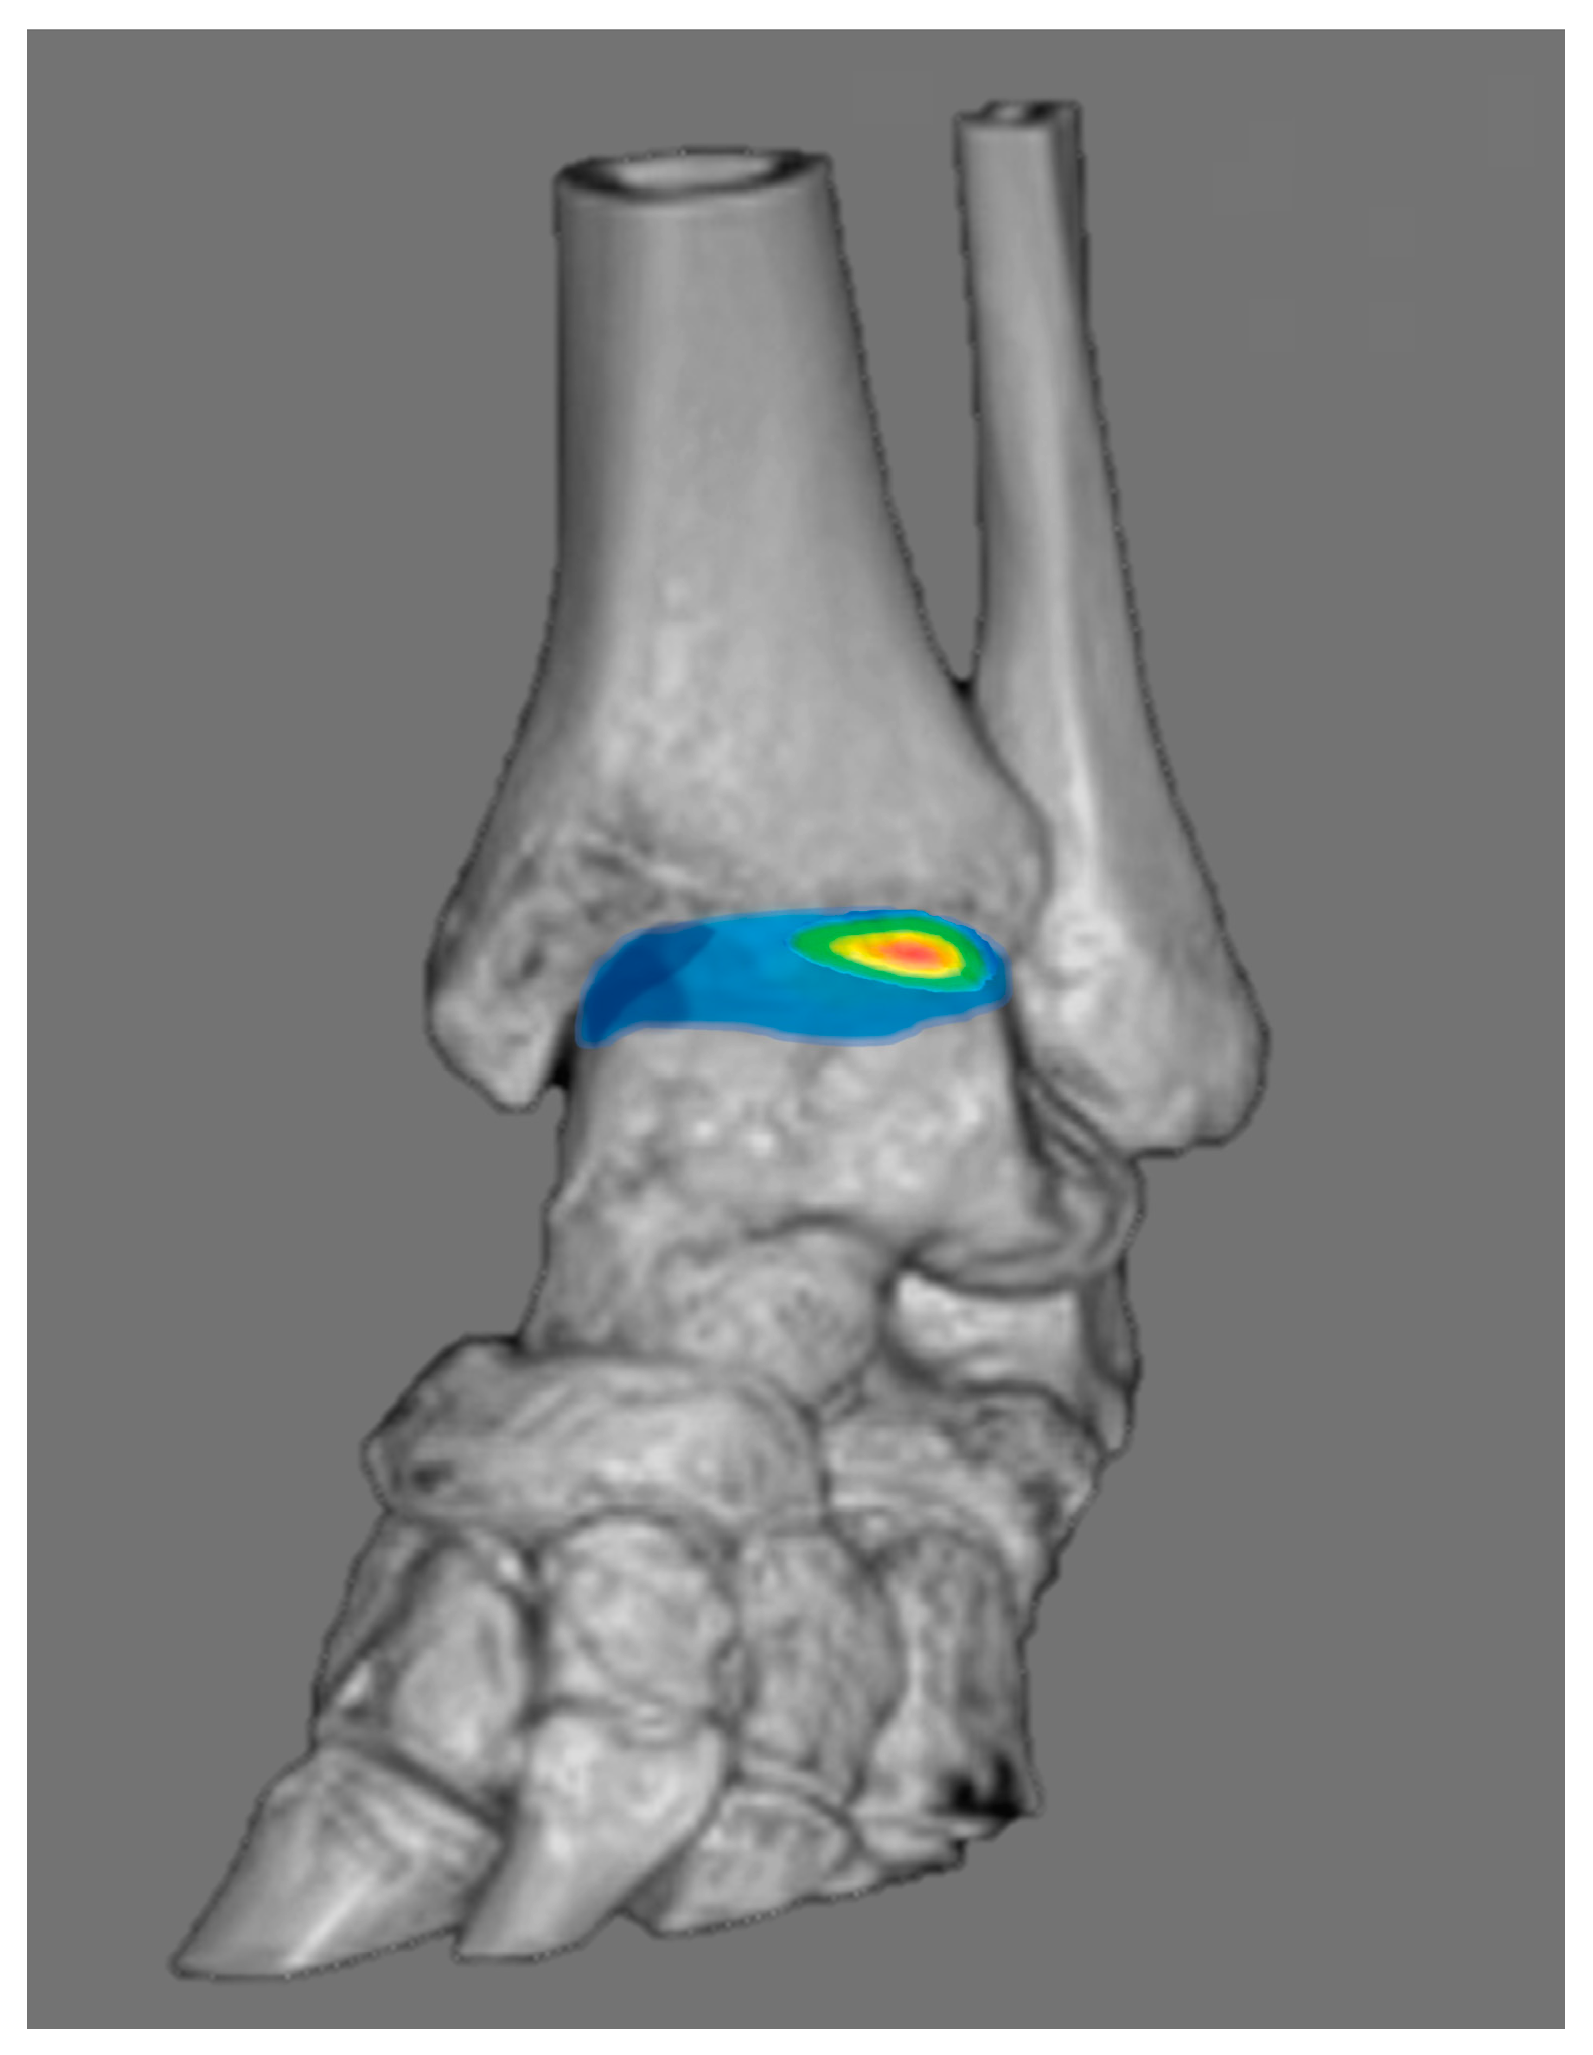

3.4. Chronic Ankle Instability

- Efrima, B.; Dahmen, J.; Barbero, A.; Benady, A.; Maccario, C.; Indino, C.; Kerkhoffs, G.; Usuelli, F.G. Enhancing precision in osteochondral lesions of the talus measurements and improving agreement in surgical decision-making using weight-bearing computed tomography and distance mapping. Knee Surg. Sports Traumatol. Arthrosc. 2024, 32, 1871–1879. [Google Scholar] [CrossRef]